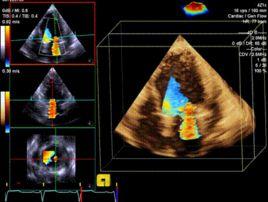

彩色都卜勒血流顯像 以彩色的亮度表??現紅藍相混的雜色。1980年代發展的新技術將血流顯色,重疊於黑白的二維或M型心動圖上,可更清楚地顯示結構異常和血液動力學異常的關係,這即是彩色都卜勒血流顯像。用自相關技術和彩色編碼處理,一般將血流朝向探頭的顯示為紅色,背向探頭的血流顯示為藍色,以色彩的亮度表示血流速度,出現渦流時,由於血流方向不同,出現紅藍相混的雜色。這樣便可以觀測心臟或大血管內血流的方向、途徑,血流性質,有無異常血流束等,可以診斷瓣膜有無狹窄、返流,有無異常的分流等(彩圖)。本法主要優點為:①快速篩選正常和異常血流,尤其是檢測異常的分流和返流;②區別發生在相同心動周期,來自不同部位而方向相似的血流,如聯合瓣膜病變的和多發性分流;③通過射流方位的顯示,指導連續波或脈衝都卜勒探測,提高定量分析心排血量及壓差的準確性;④對返流和分流病變,可提供簡便的半定量診斷方法。不足之處是二維結構顯象的質量因幀數減少而降低。